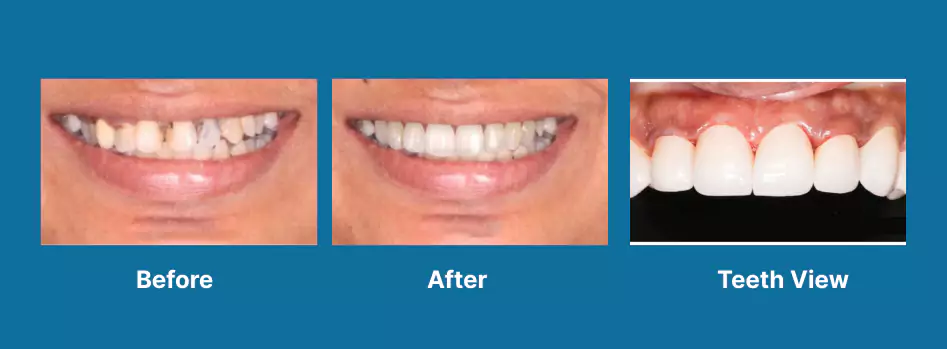

Esthetics

Full Mouth Rehabilitation